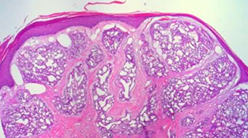

Vascular neoplasm: Intermediate

KAPOSI SARCOMA

Reddish macules that become raised plaques and nodules over time; begins in skin GROSS

Dilated blood vessels with an endothelial mononuclear infiltrate; will progress to see spindle cells with hyaline globules, mitotic figures, and hemosiderin pigment MICROSCOPY